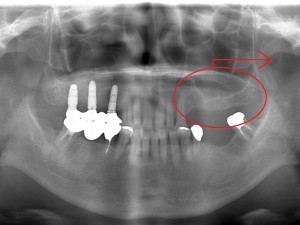

60代 男性 インプラント症例

60代 女性 S様

上下入れ歯の患者様です。入れ歯に違和感があったため来院されました。

右上3本、左上3本、左下2本のインプラントを埋入。

右上は骨が足りない為サイナスリフトをしてインプラント手術を行いました。

術前のレントゲン写真